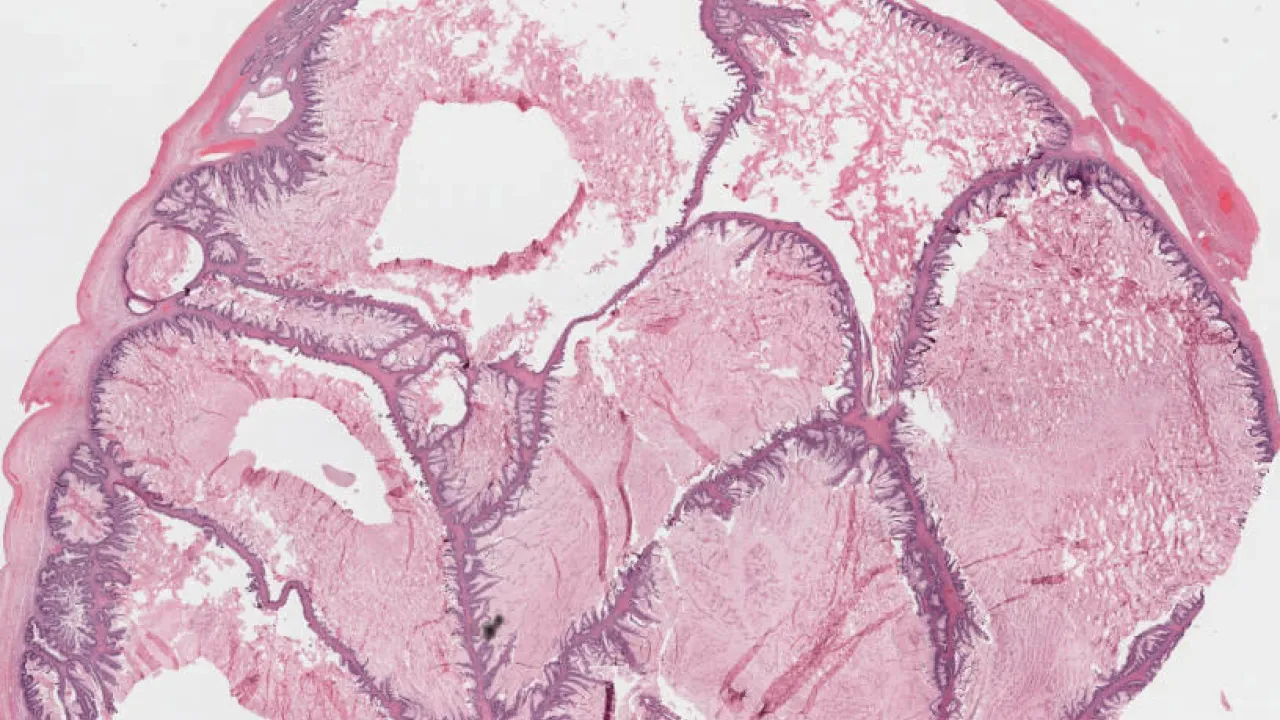

Pancreas, Intraductal papillary mucinous neoplasm